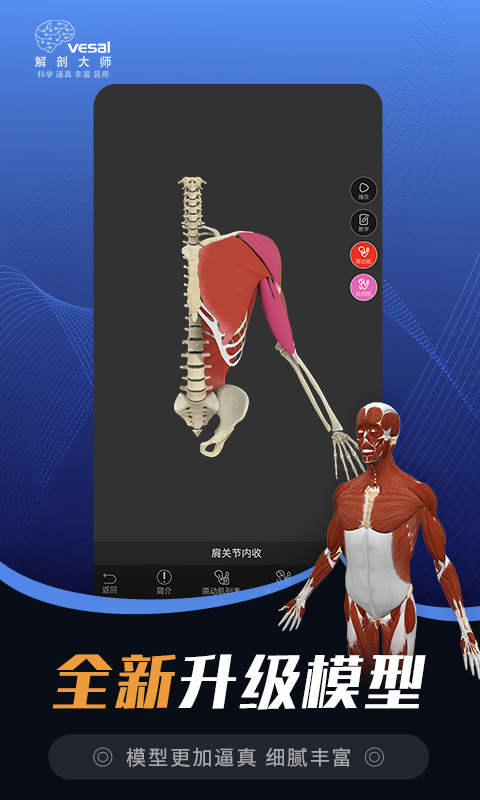

——运动解剖—— 3D运动分析工具

关节运动、肌骨系统(肌肉功能视频,肌肉动作,肌肉起止点,肌肉拉伸锻炼),Yoga瑜伽库为每日瑜伽打卡锻炼提供指导,适合瑜伽锻炼,减肥锻炼;健身库可用于肌肉锻炼运动打卡,作为健身游戏,减肥操,产后瘦身,在家运动;康复方案库、运动原理(提供经典动作的解剖学分析,投篮球、排球扣球等)